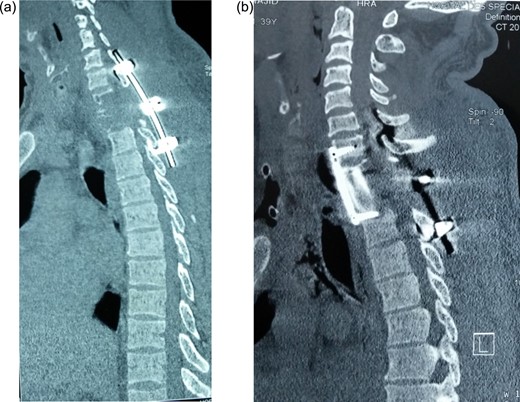

Postoperative sagittal CT showing (a) hook and rod stabilization posteriorly, and (b) bone graft and plate fixation anteriorly after corporectomy of D1 and D2.

Given this diagnosis, a second-stage surgery was performed 2 weeks later. This was performed by an anterior approach whereby cervicothoracic incision extending from lower cervical (C6) to upper thoracic (D3) was performed. It involved detachment of two heads of sternocleidomastoid muscles on the right side, and medial third of right clavicle was excised. The innominate artery and superior vena cava were identified and retracted exposing pathological vertebrae. Corpectomies of D1–D2 carried out, and residual tumor on posterior longitudinal ligament (PLL) and other surrounding structure was excised. Strut graft from the clavicle was placed to bridge the defect and stabilized by anterior plate bridging between C7 and D3.